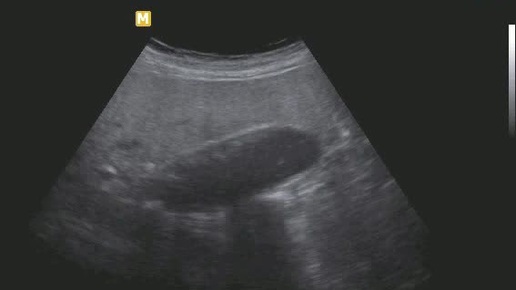

Ультразвуковые находки от врача УЗД Зорина Я.П.